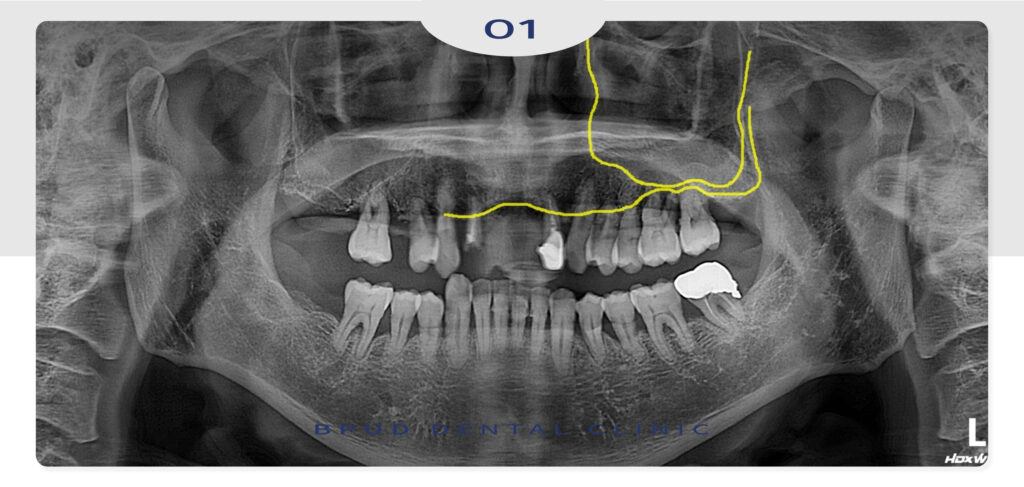

환자분은 50대 중반의 남성분으로

지인 분의 소개로 부평임플란트를 위해

내원해 주셨는데요.

비용적인 문제로 내원을 미루다

오셨다는 말씀을 해주셨습니다.

전체적으로 잇몸이 좋지 않음을 알 수 있었고

환자분께서는 한쪽만이라도 부평임플란트 식립을

진행하여 식사를 하실 수 있도록 하는 것을 원하셔서

상악동 거상술 및 임플란트와 부러진 앞니 임플란트

식립 계획을 수립하였습니다.

왼쪽 위 어금니 부위는 골소실이 많이

진행되어 상악동 거상술을 통해

많은 양의 뼈를 이식하여 임플란트를

진행하시기로 하였는데요.